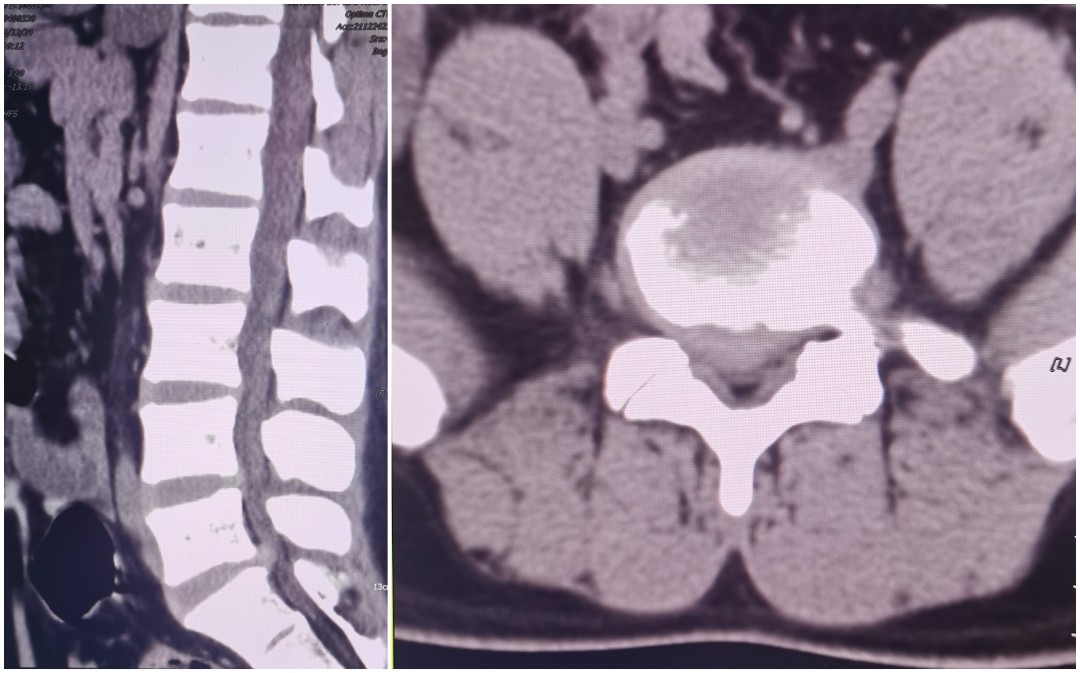

患者陈某,中年女性,反复腰痛9年余,加重伴左下肢放射痛、麻木1月入院,查体:脊柱生理弯曲存在,腰部未扪及台阶感,腰椎间隙稍压痛,椎旁肌压痛及叩击痛,左下肢稍萎缩,左下肢肌力4级,左大腿、小腿外侧及足背外侧感觉麻木,左侧膝反射及跟腱反射减弱,右下肢肌力感觉正常,双下肢肌力正常,结合辅助检查,诊断:腰4/5椎间盘突出症,于全麻行MIS-TLIF入路腰4/5髓核摘除、椎管扩大减压神经根松解、椎间融合器植骨融合内固定术,术后第二天佩戴护具下床活动,恢复良好。

术前影像学